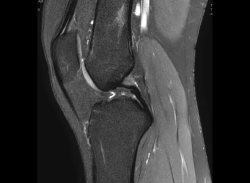

Resonancia magnética

Se basa en la propiedad que poseen los núcleos de hidrógeno de absorber energía electromagnética cuando están sometidos a un campo magnético intenso. La RM representa un mapa de la densidad de protones, o sea, de la distribución de agua por el organismo(12).

Se consiguen unas imágenes de alta resolución para la valoración de meniscos, ligamentos y tendones. Además, es especialmente útil en las rodillas operadas, lesiones tumorales, evaluación del cartílago y la visualización de los nervios(13).

4. Lesiones isquémicas

4.1. Necrosis avascular (NAV)

En la NAV (aséptica, isquémica u osteonecrosis), hay una pérdida del flujo de sangre en el tejido óseo que hace que el hueso muera.

Se produce por un trastorno de la irrigación sanguínea o por lesiones celulares en el hueso y en la médula ósea.

Puede observarse en la RM la disminución de la intensidad de la lesión mucho antes de que se aprecie con otras pruebas diagnósticas (Figura 51).

4.3. Osteocondritis

En la osteocondritis se aprecia una lesión subcondral caracterizada por resorción ósea, colapso y la formación de un secuestro.

El estudio por RM es una herramienta valiosa para diagnosticar e identificar las lesiones del cartílago. Conocer el aspecto del cartílago y saber cuánto y cuándo se lesiona, basándose en las clasificaciones actuales, permiten al radiólogo proporcionar la máxima información al clínico(20).

Figura 53. Corte de secuencia sagital (A) y axial (B) T2 Fat-Sat de RM de rodilla: lesiones osteocondrales en el fémur y la rótula.

Numerosos estudios demuestran la utilidad de la RM para definir la estabilidad o inestabilidad de la lesión en la osteocondritis, destacando su carácter no invasivo y la capacidad de valorar la progresión y la respuesta al tratamiento(21)(Figuras 53 y 54).